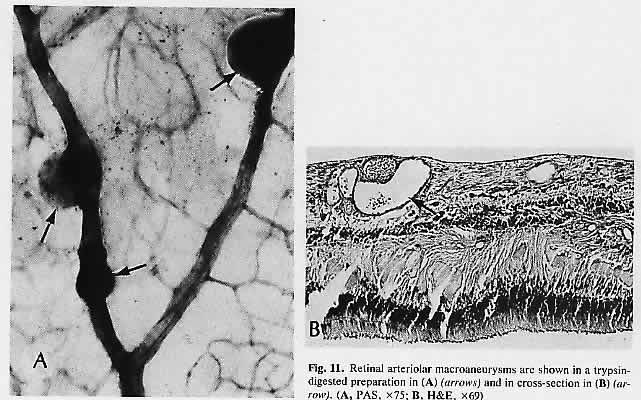

of ophthalmoscopically visible lesions. Arch Ophthalmol 90:49, 1973 31. Zimmerman LE: Embolism of central retinal artery. Arch Ophthalmol 73:822, 1965 32. Gartner S, Henkind P: Neovascularization of the iris (rubeosis iridis). Surv Ophthalmol 22:291, 1978 33. Enzenauer RJ, Stock JG, Enzenauer RW et al: Retinal vasculopathy associated with systemic light chain deposition disease. Retina 10:115, 1990 34. Wolter JR: Axonal enlargements in the nerve-fiber layer of the human retina. Am J Ophthalmol 65: 1, 1968 35. Ashton N, Harry J: The pathology of cotton wool spots and cytoid bodies in hypertensive retinopathy